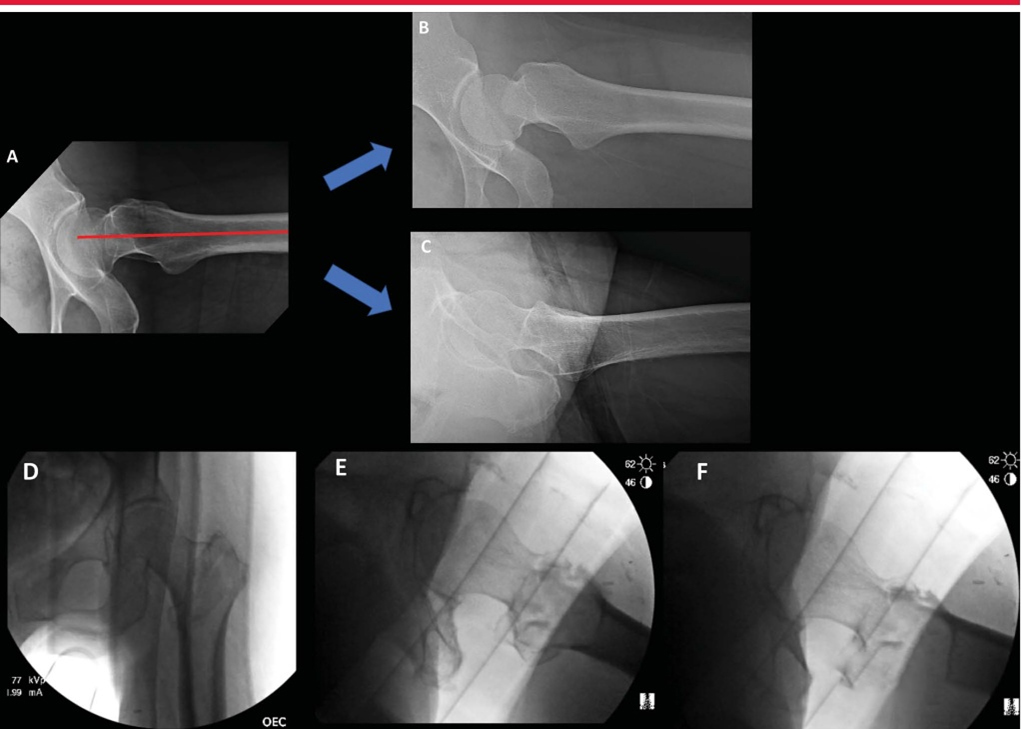

Интраоперационная боковая рентгеноскопия бедра для оценки репозиции и имплантата. А. Боковое изображение, наиболее подходящее для имплантата, демонстрирующее коллинеарность головки, шейки бедренной кости и оси бедренной кости. Б. Боковая рентгенограмма того же тазобедренного сустава во внутренней ротации. C: Повернутое наружу боковое изображение того же бедра, оптимальное для оценки переднемедиальной кортикальной поддержки и репозиции вертельных переломов. D–F: интраоперационные рентгеноскопические изображения, полученные в положении лежа на столе для переломов, показывающие вид в прямой проекции (D), боковой вид имплантата (E) и боковой репозиции (F).